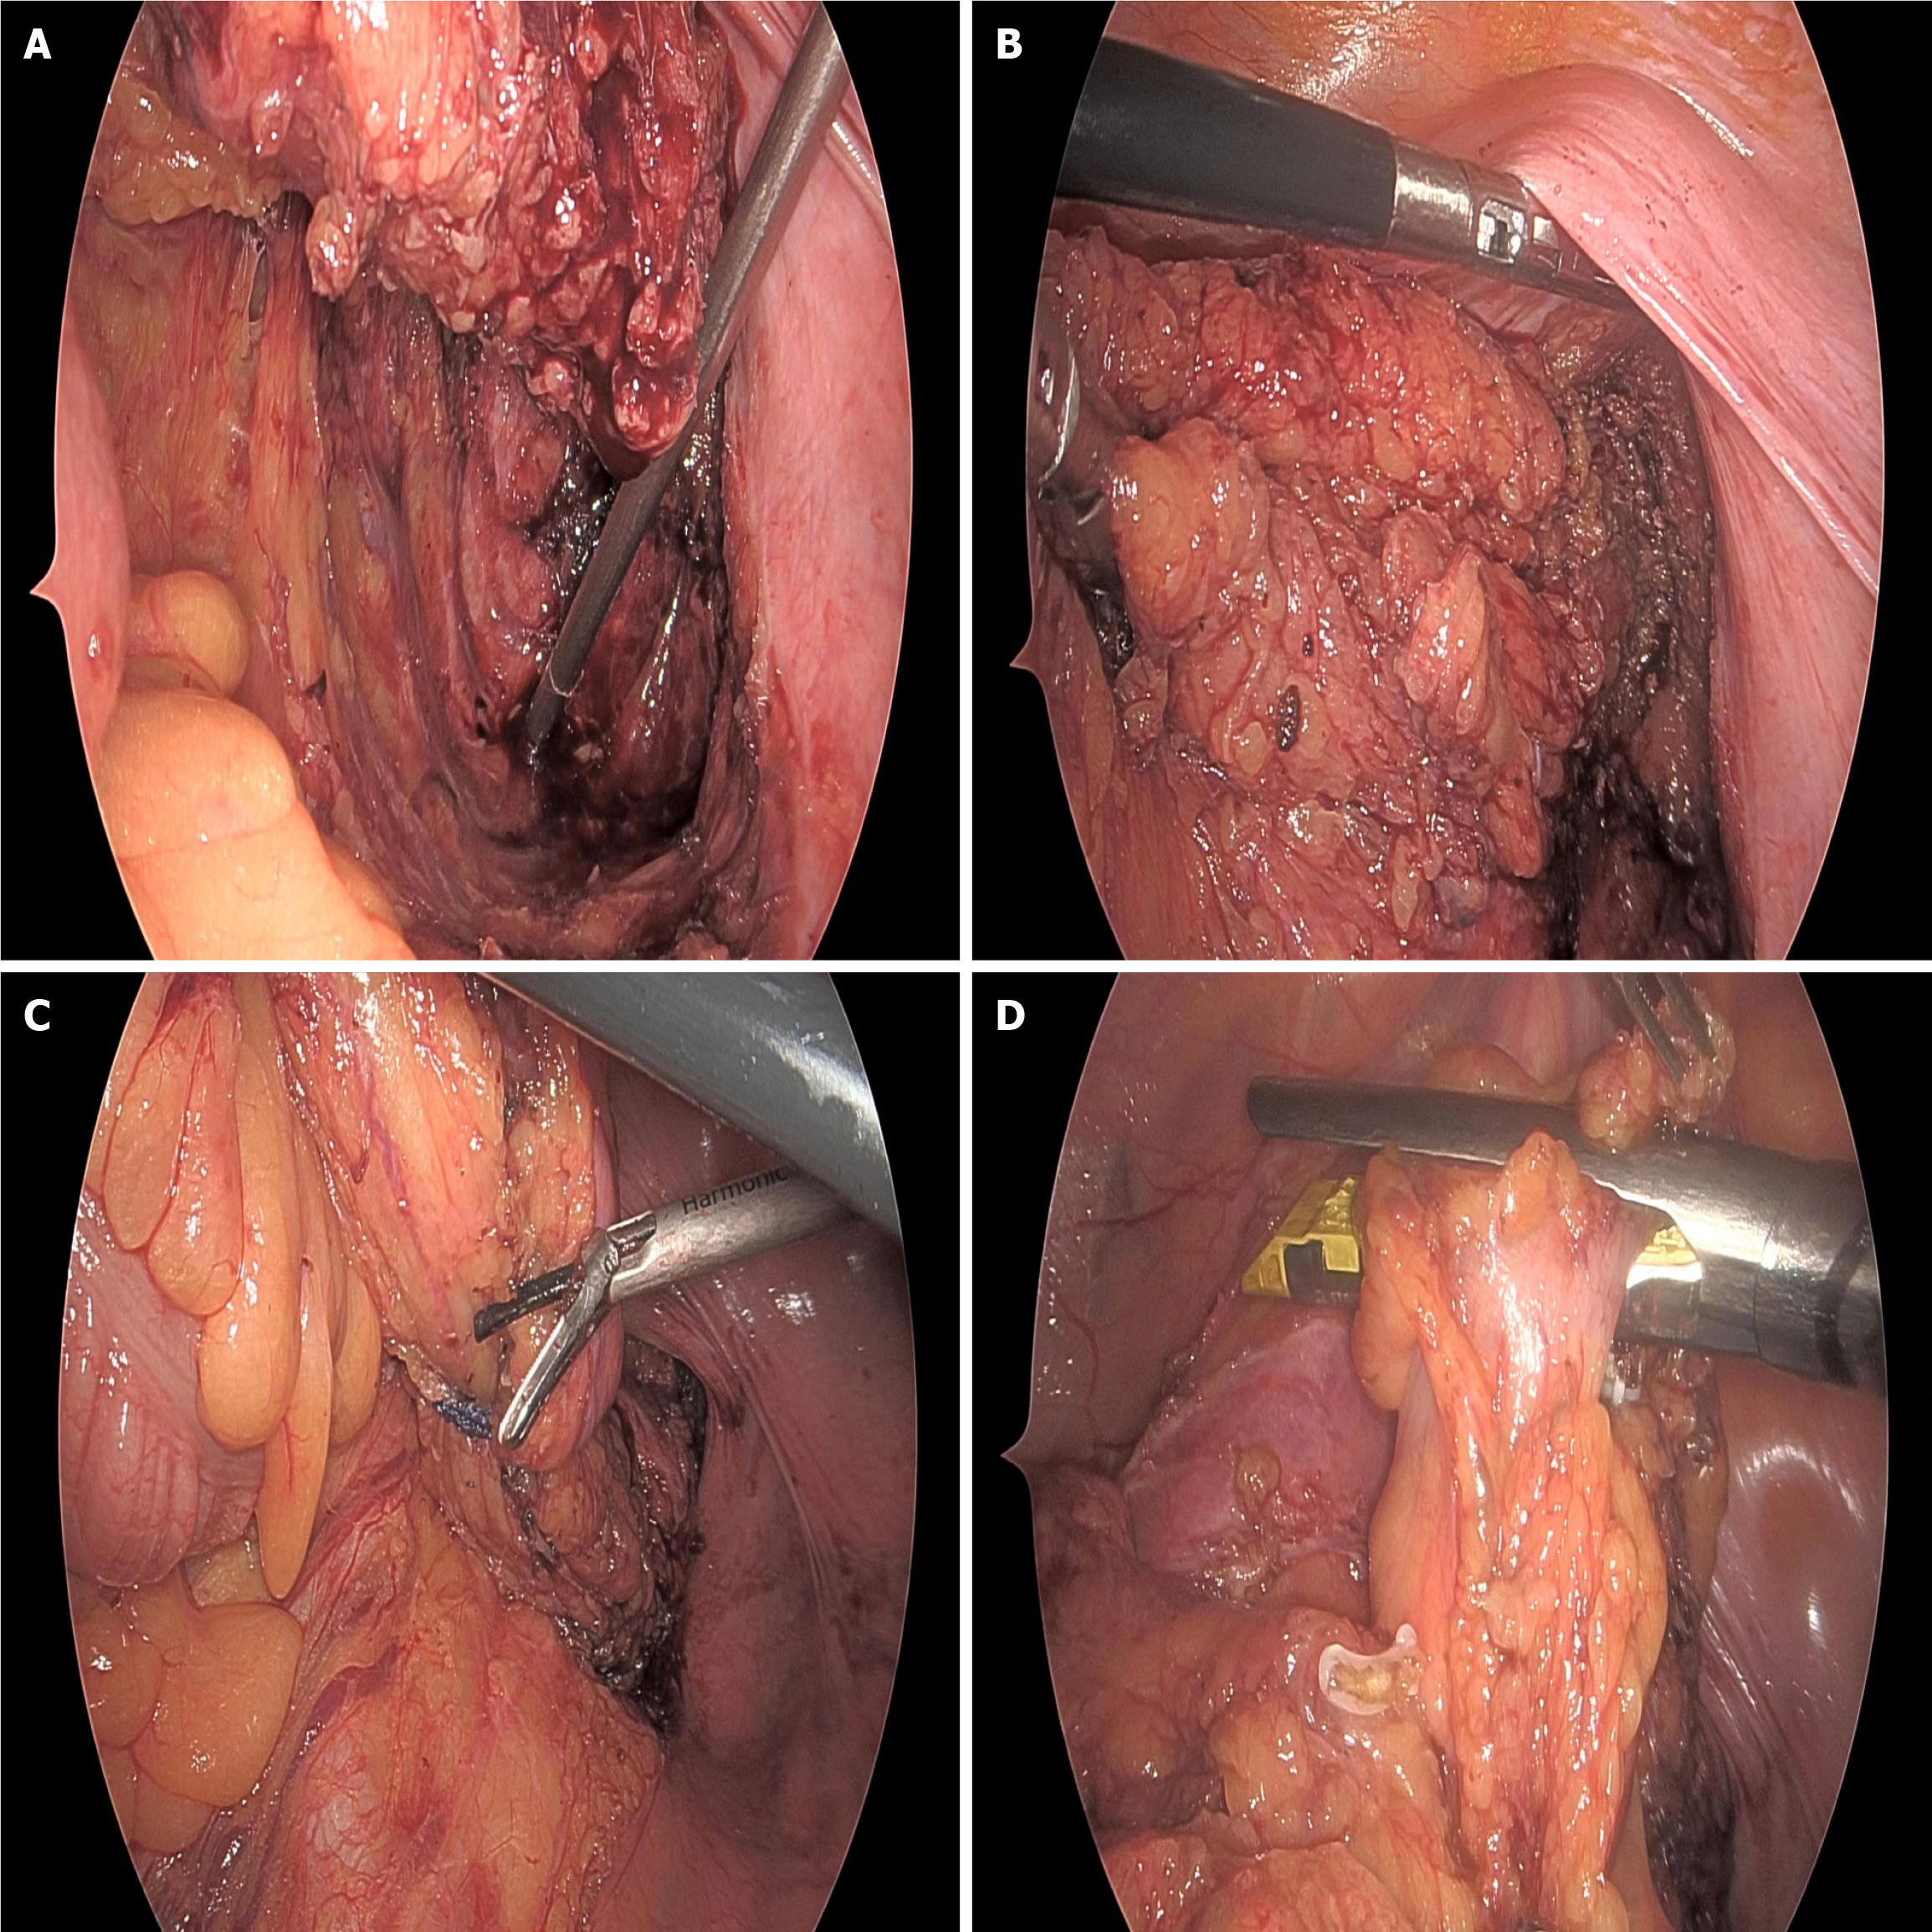

Surgical methods: Surgical approaches were selected based on tumor location, clinical staging, and patient-specific conditions. For mid and high rectal cancer patients with tumors > 5 cm from the anal verge, laparoscopic-assisted resection was preferentially performed, strictly adhering to the total mesorectal excision principle to ensure negative circumferential margins and thorough lymph node dissection. The surgery employed a five-port technique, including one observation port (10 mm above the umbilicus) and four operating ports (5 mm-12 mm in the lower abdomen and both lateral abdominal regions). Ultrasonic scalpels and laparoscopic linear cutters were used to ensure surgical precision when mobilizing the colon and transecting mesenteric vessels. For low rectal cancer patients ≤ 5 cm from the anal verge, after fully assessing the relationship between the tumor lower margin and the anal sphincter, a laparoscopic low anterior resection (Dixon procedure) was performed for those likely to preserve anal sphincter function, with prophylactic ileostomy when necessary; for those unable to preserve anal function, abdominoperineal resection (miles procedure) was adopted. All patients underwent D2/D3 lymph node dissection as recommended by the Japanese Society for Cancer of the Colon and Rectum. Surgical specimens were marked with distal, proximal, and circumferential margins to ensure radical surgery. Intraoperative records included surgery time, blood loss, incision length, and other surgery-related indicators. Anastomosis was chosen based on tumor location, with end-to-end or side-to-end anastomosis completed using directional stapling technology staplers or manual sutures. For cases with local infiltration or severe adhesions found intraoperatively, the resection range was appropriately expanded under the premise of surgical safety, and multi-organ resection was performed when necessary (Figure 1).